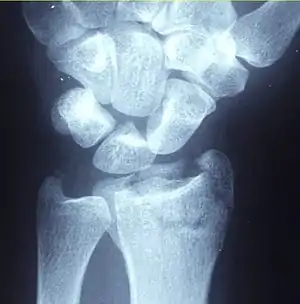

A distal radius fracture, also known as wrist fracture, is a break of the part of the radius bone which is close to the wrist.[1] Symptoms include pain, bruising, and rapid-onset swelling.[1] The ulna bone may also be broken.[1]

In younger people, these fractures typically occur during sports or a motor vehicle collision.[2] In older people, the most common cause is falling on an outstretched hand.[2] Specific types include Colles, Smith, Barton, and Chauffeur's fractures.[2] The diagnosis is generally suspected based on symptoms and confirmed with X-rays.[1]

Diagnosis may be evident clinically when the distal radius is deformed, but should be confirmed by X-ray. The differential diagnosis includes scaphoid fractures and wrist dislocations, which can also co-exist with a distal radius fracture. Occasionally, fractures may not be seen on X-rays immediately after the injury. Delayed X-rays, X-ray computed tomography (CT scan), or Magnetic resonance imaging (MRI) can confirm the diagnosis.